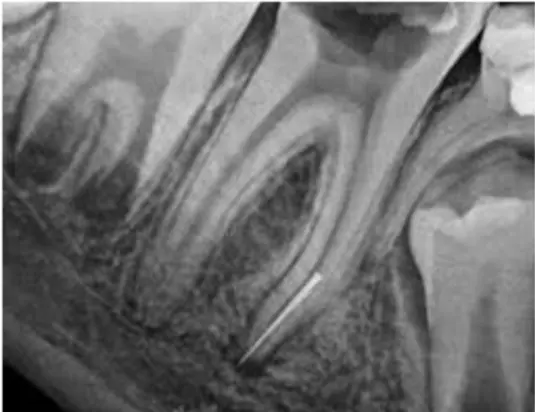

File Retrieval

Mengeluarkan file atau alat khusus perawatan saraf gigi berukuran kecil yang patah dan tertinggal di dalam saluran akar gigi.